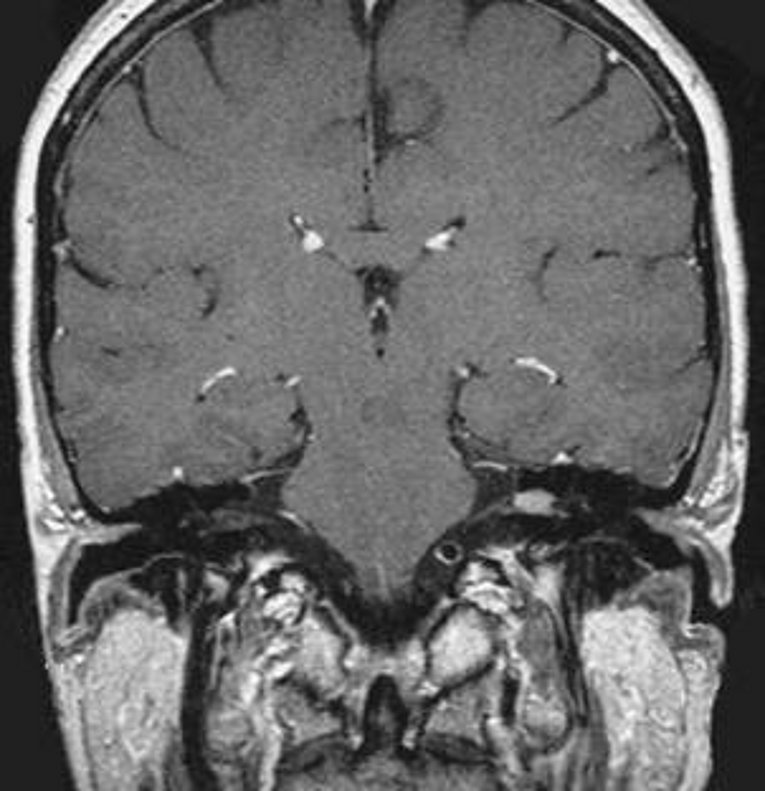

Unser Erfahrung nach sind eine Gleichgewichtsprüfung und BERA sehr gut als Screening-Methoden geeignet. Allerdings kommen immer häufiger Patienten mit kleinen Tumoren, einem normalem Gehör und unauffälliger Kalorik. Deshalb ist die Bildgebung, insbesondere die Kernspintomographie als Goldstandard in der Diagnostik des Akustikusneurinoms anzusehen.

Schema: Abbildung der Größenverteilung von neu diagnostizierten Akustikusneurinomen. Deutlich erkennt man eine Zunahme von kleinen Tumoren der Größe A (hellblau) bei gleichzeitiger Abnahme der Anzahl von großen Tumoren der Größe C (nach Wigand).